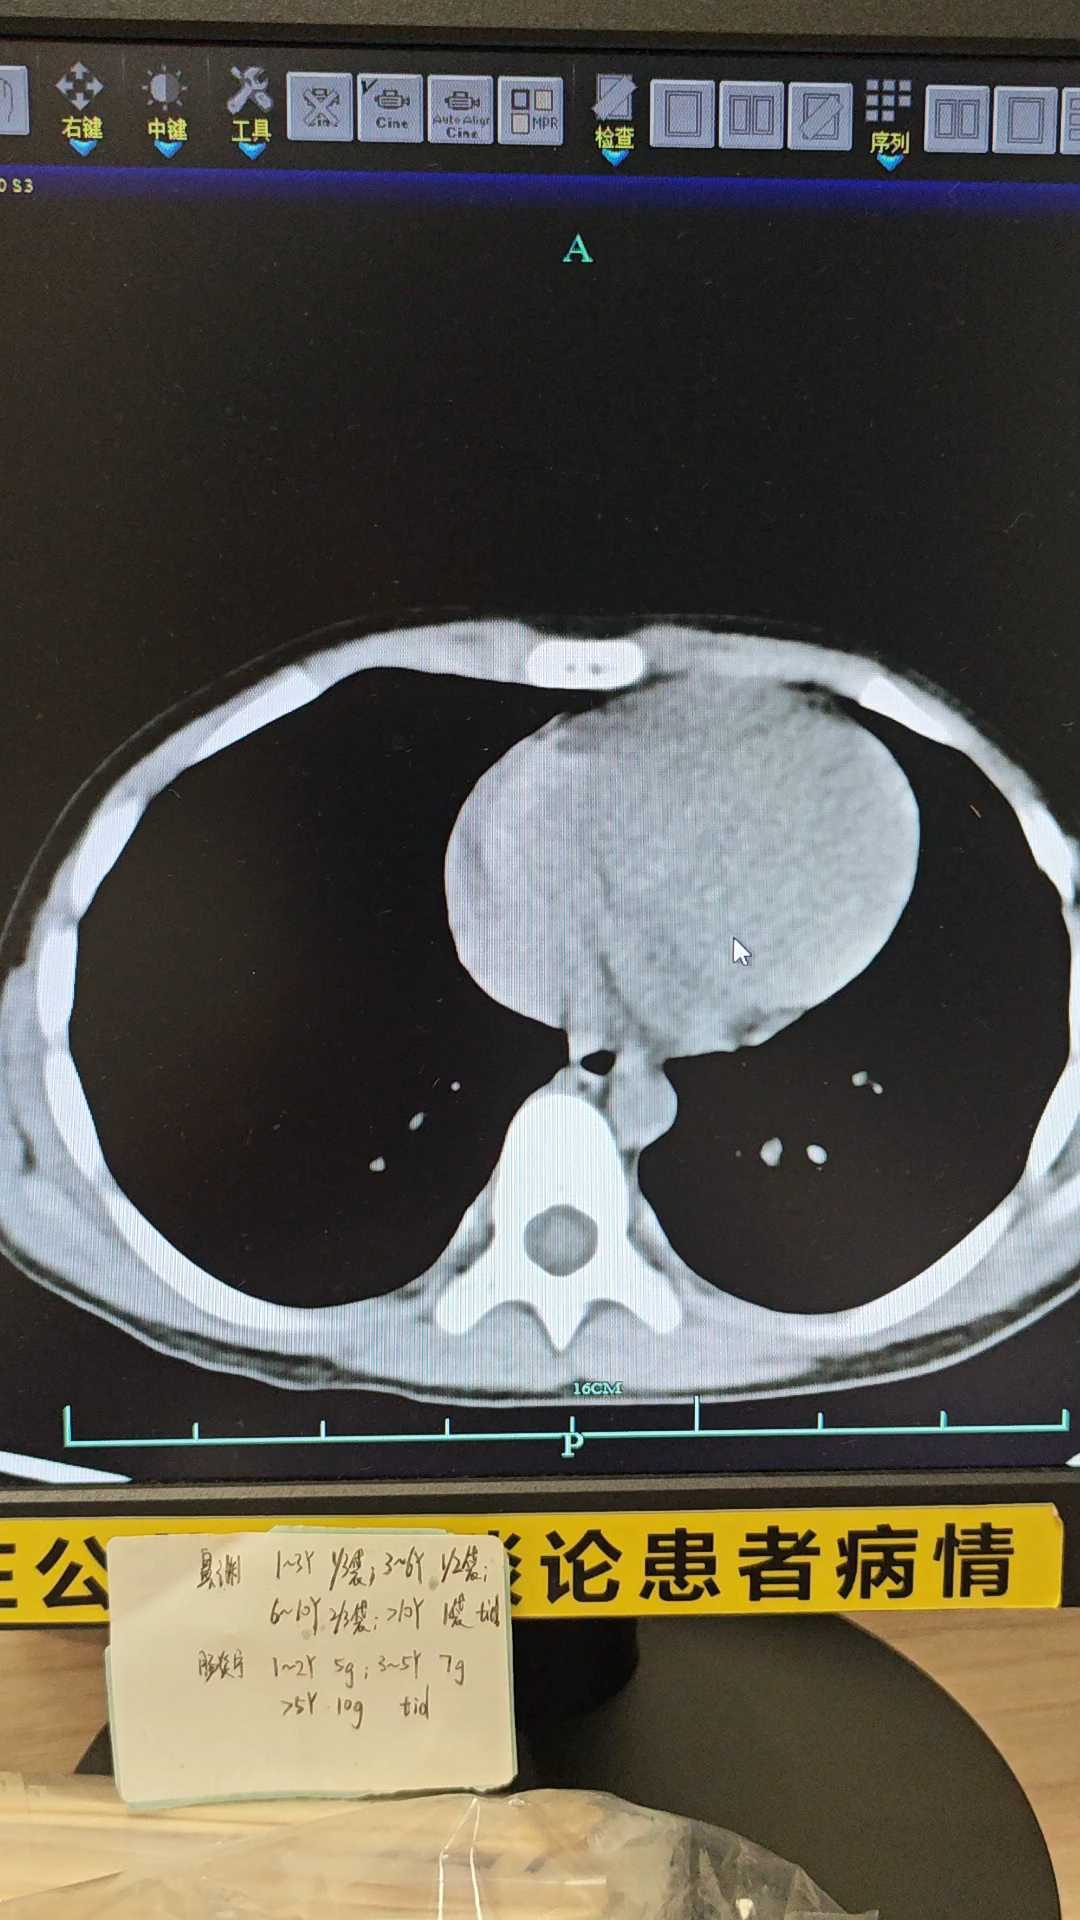

患儿4岁,3天前进食外卖(一起进食的孩子有多人发病,表现腹痛呕吐腹泻)后出现腹痛呕吐,无发热,大便未解。一天前腹痛加重,呕吐一天2-3次。纳差,精神欠佳。查体 生命体征稳定,痛苦貌,全腹稍紧张,两下腹压痛明显。

腹部CT不会看,请老师们看看,临床考虑什么,治疗方案。